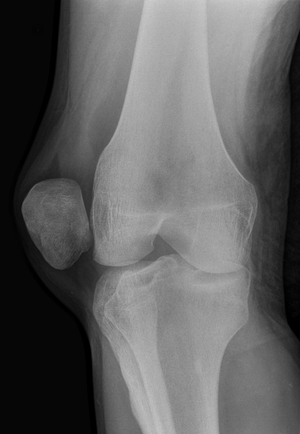

[[File:Patellar dislocation.jpg|thumb|patella dislocates laterally]] | [[File:Patellar dislocation.jpg|thumb|patella dislocates laterally]] | ||

*Patella is usually displaced laterally; knee is held in flexion | *Patella is usually displaced laterally; knee is held in flexion | ||

- Patella is usually displaced laterally; knee is held in flexion